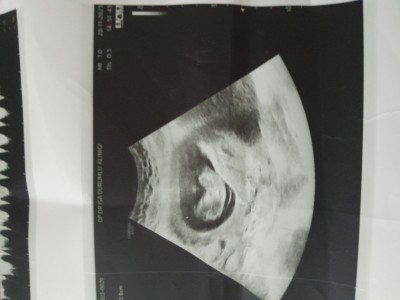

Sadece can sıkıntısı cinsiyet tahmini :)

Haydi bakalımmmmm

Erkek geçti gönlümden

İçimden erkek geçti ama kaç haftalık daha minik gibi duruyor ❤️

11+3 canım .doktor da erkek gibi ama bidakine netleşir dedi :)